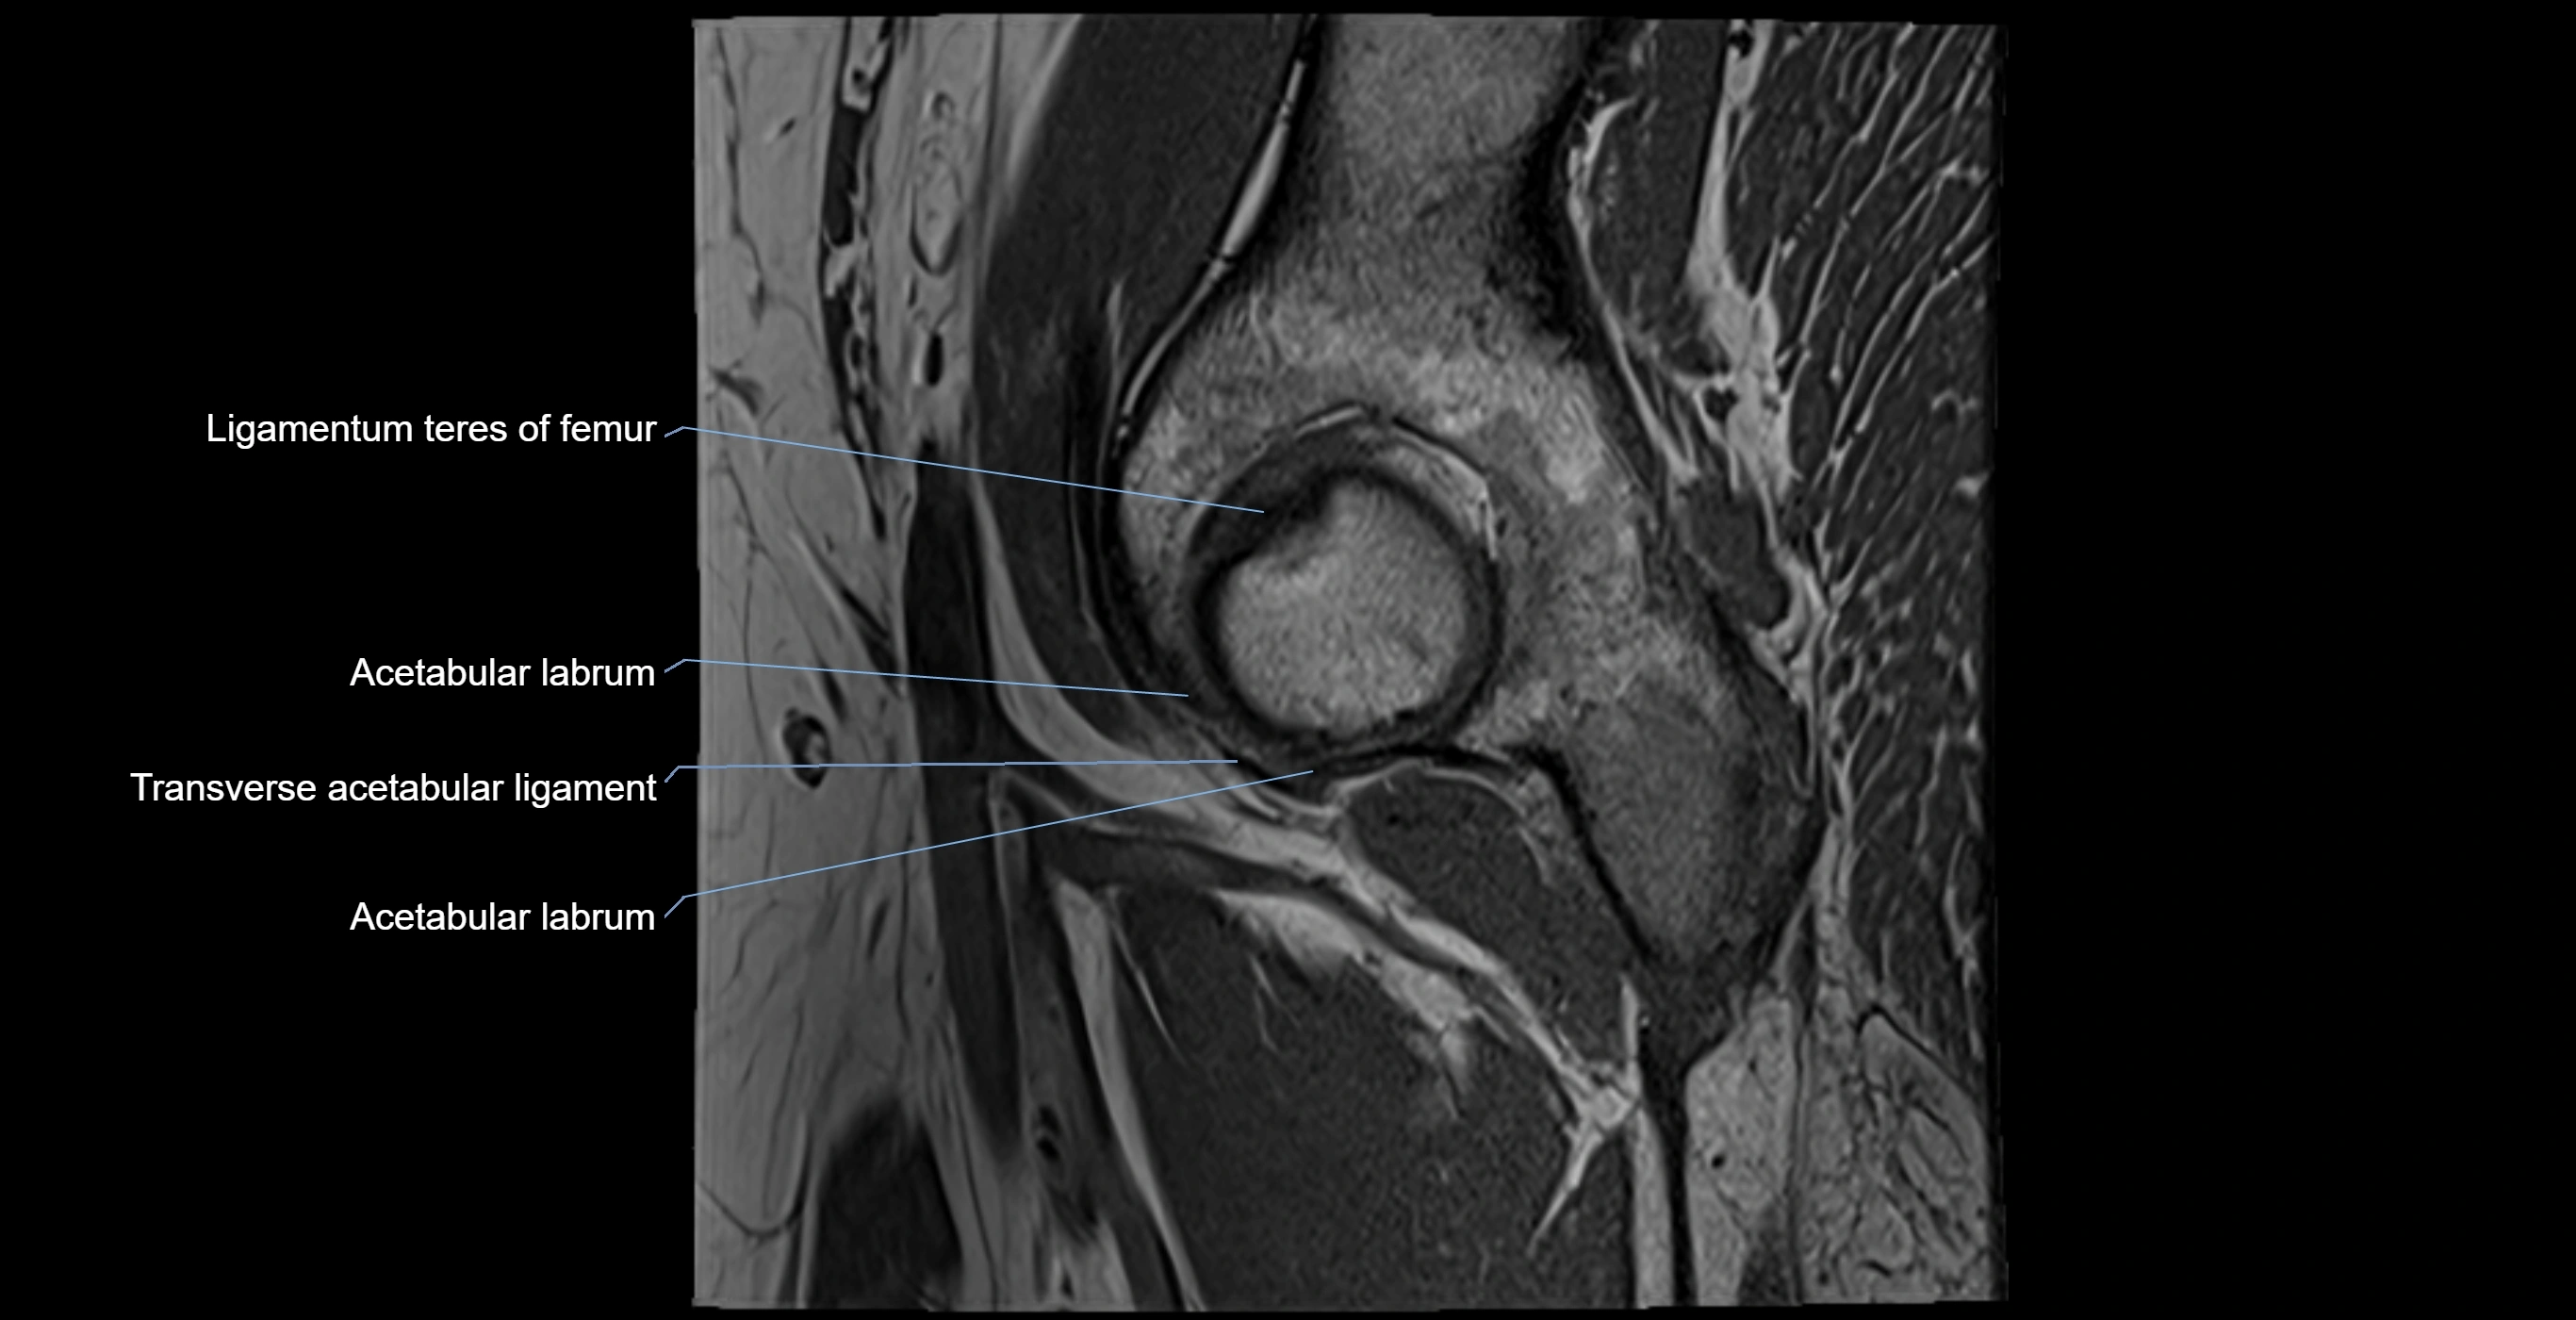

Acetabular labrum

The acetabular labrum is a fibrocartilaginous ring that surrounds the rim of the acetabulum in the hip joint. It deepens the hip socket, increases joint stability, and maintains a suction seal that preserves negative intra-articular pressure. Structurally, the labrum transitions from hyaline cartilage of the acetabulum to dense fibrocartilage at its free edge.

It is triangular in cross-section, with its base attached to the acetabular rim and its apex projecting toward the femoral head. The labrum is most robust superiorly and anteriorly, where load bearing is greatest, and relatively thinner inferiorly.

Structure and Relations

• Superior and anterior labrum: thickest portions, stabilizing against anterior dislocation

• Inferior labrum: blends with the transverse acetabular ligament bridging the acetabular notch

MRI Appearance

T1-weighted images:

• Labrum: low signal intensity (dark)

• Surrounded by intermediate signal joint fluid (bright on arthrogram)

• Tears: linear or focal areas of intermediate-to-high signal interrupting labral continuity

T2-weighted images:

• Joint fluid: bright, making labral tears visible as fluid extending into or around labrum

• Degeneration: may show areas of increased signal within labrum

MRI image

image